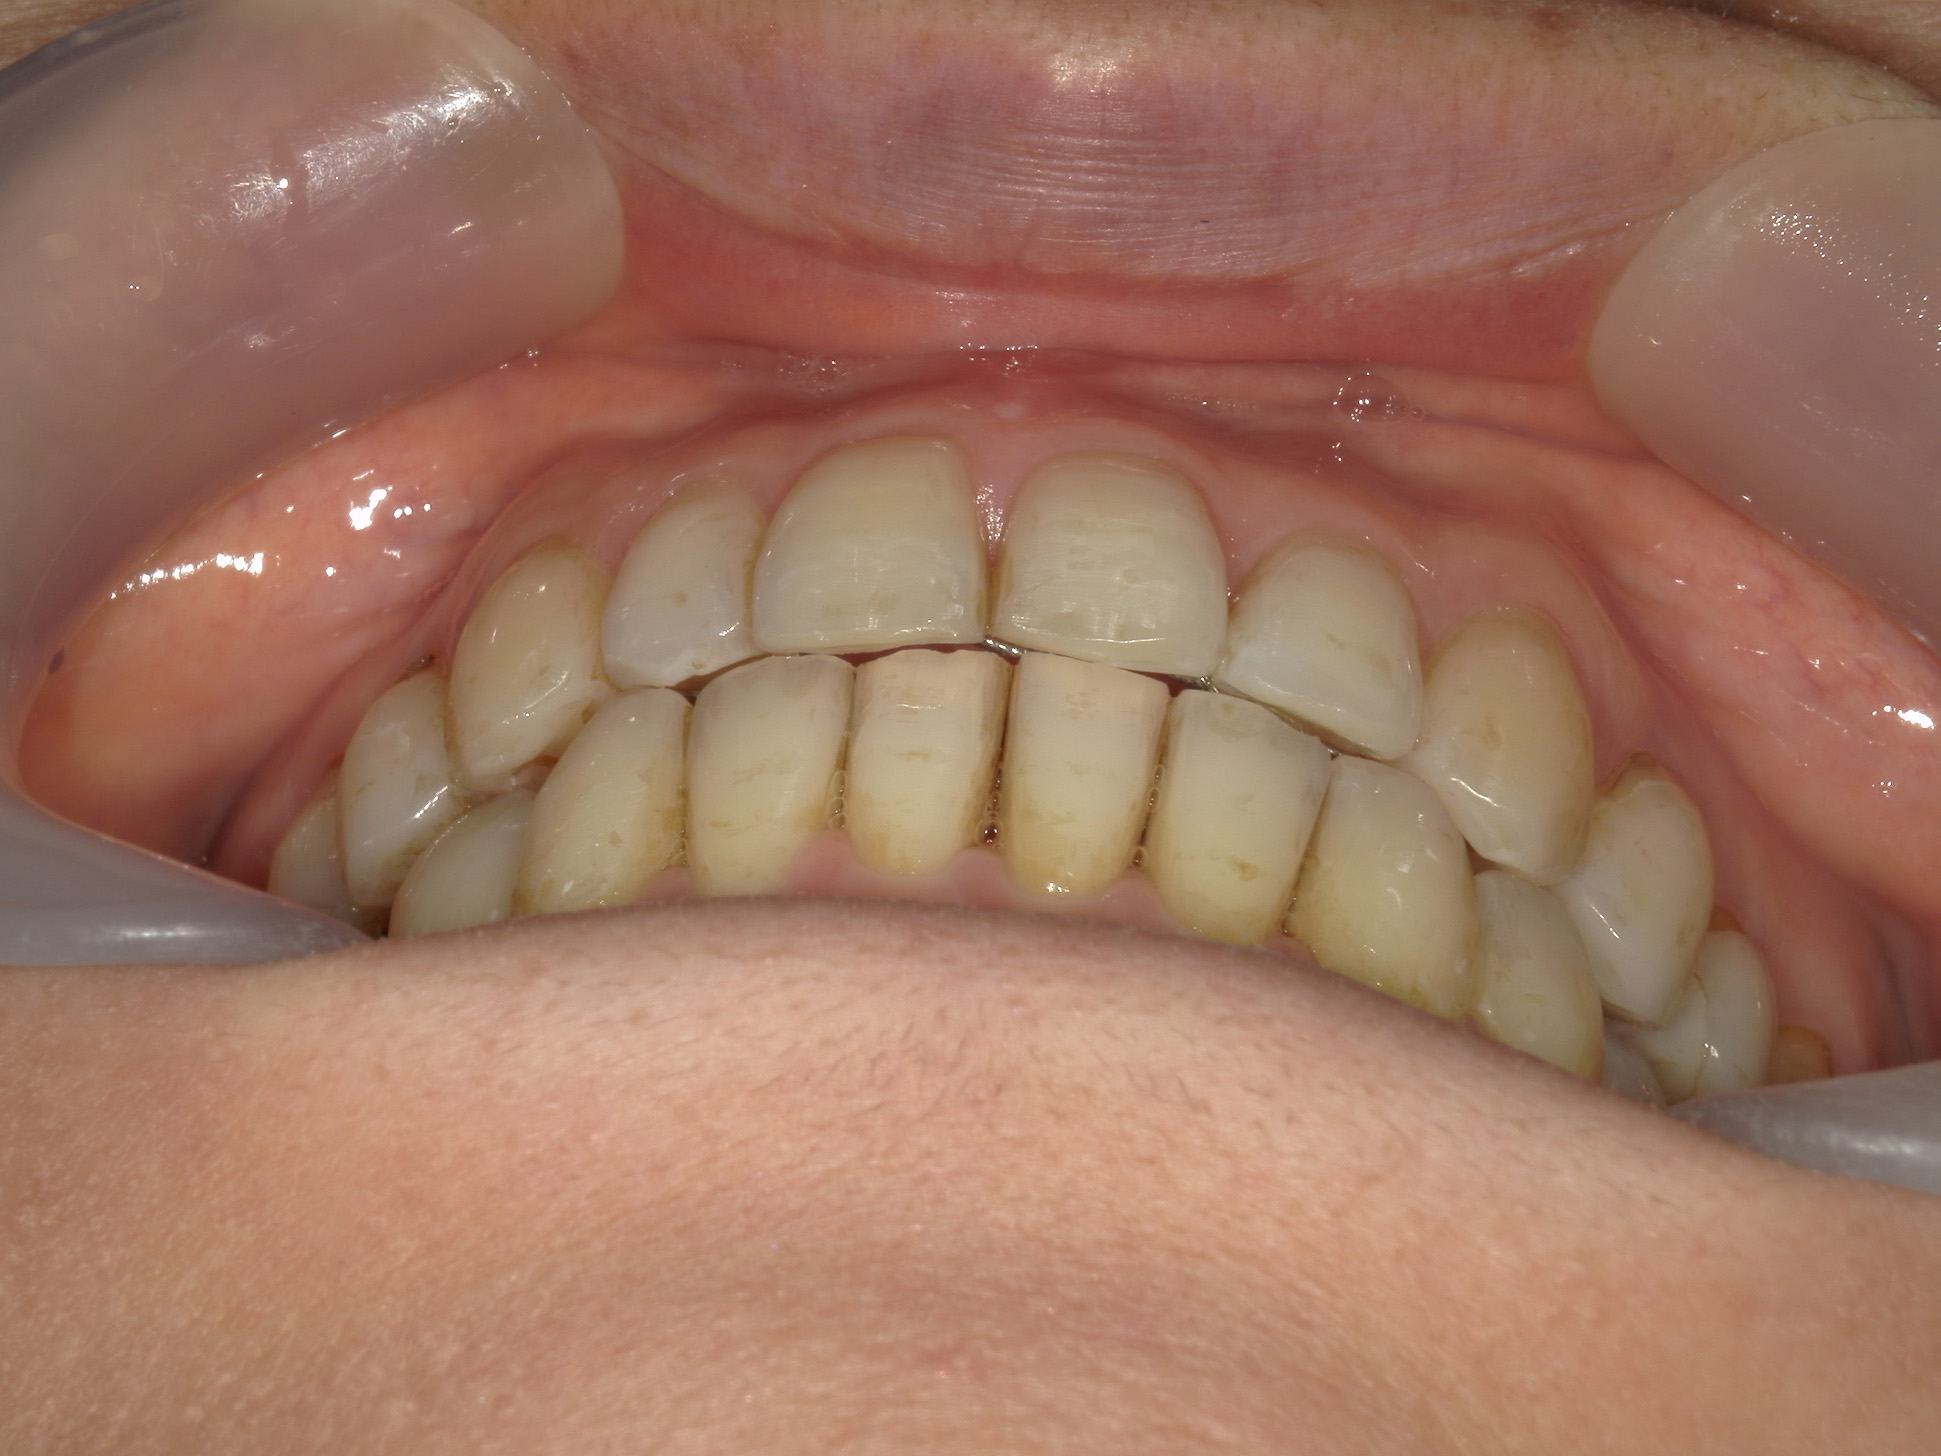

インビザライン矯正 症例(25)

主訴: ㊤前歯が出ていて、噛み合わせが気になる。

カテゴリー : ガタガタ(叢生)